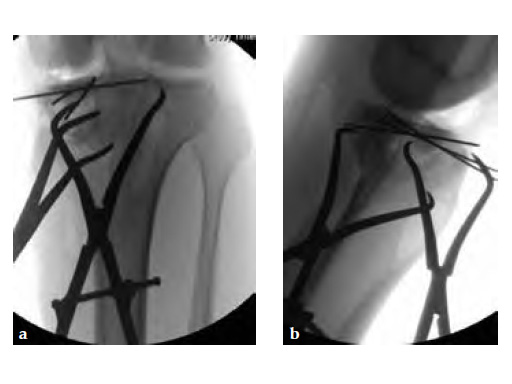

Initially taken for incision and drainage and then ORIF . Patient placed in a floppy lateral position with the effected lower extremity externally rotated (opposite hip and shoulder bumped up about 3040) allowing exposure of the posterior medial knee. A posterior medial and an anteromedial incision were used to repair the fracture with a 67 cm skin bridge.